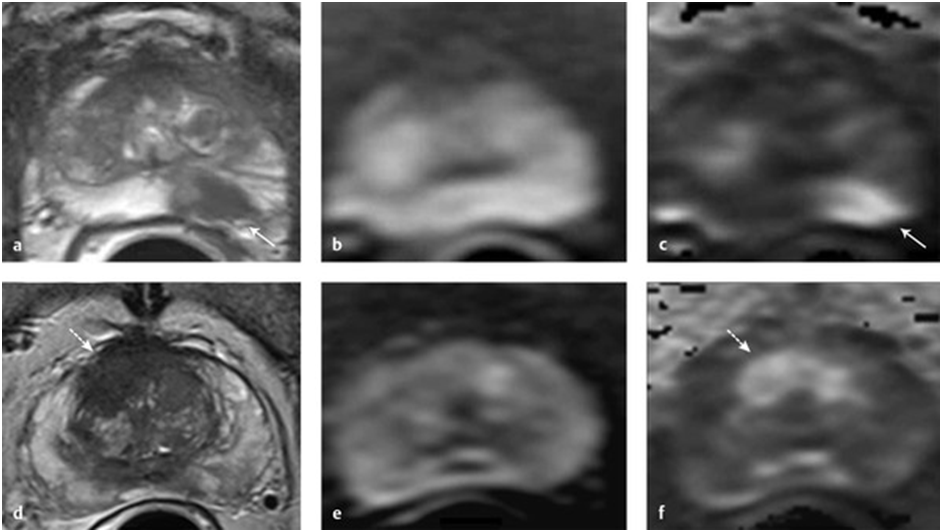

Для диагностики опухолей обычно используется высокий b-фактор (больше 1000, оптимально больше или равно 1400), который позволяет обнаружить сниженную диффузию в местах, где клеточная плотность аномально увеличена, а объем внеклеточной жидкости уменьшен. При меньшем b-факторе диффузионного взвешивания недостаточно для обнаружения таких аномальных зон, т.к. начинает преобладать Т2-взвешивание (эффект Т2-просвечивания). Это выражается в зонах высокого сигнала там, где ограничения диффузии на самом деле нет.

a, d – Т2-серия, b, e – DWI b-value 1000, c, f – DWI b-value 1600 [8]

Однако, получение DWI с высоким b-фактором непосредственно на томографе затруднительно, т.к. для получения изображений с достаточным качеством и без артефактов требуется или значительное увеличение времени сканирования, или использование более мощных томографов или специальных катушек. Поэтому часто такие серии создаются аналитически путем экстраполяции кривых затухания сигнала на основе набора данных с более низкими b-факторами. Один из алгоритмов – линейная экстраполяция логарифма значений пикселей.

Во многих публикациях отмечено, что подобные синтетические серии более информативны, чем оригинальные, т.к. с ростом b-фактора, к тому же, снижается уровень шума.

Для DS-задач синтезирование DWI-серий целесообразно еще и по причине уменьшения влияния разнородности исходных данных на результаты, т.к. в разных исследованиях могут встречаться разные наборы b-факторов.

Однако b-фактор не столь однозначный параметр, как хотелось бы. Одному и тому же его значению могут соответствовать разные комбинации параметров градиентных импульсов, лучше или хуже выделяющие те или иные ткани. Поэтому и изображения могут сильно отличаться друг от друга. [6]